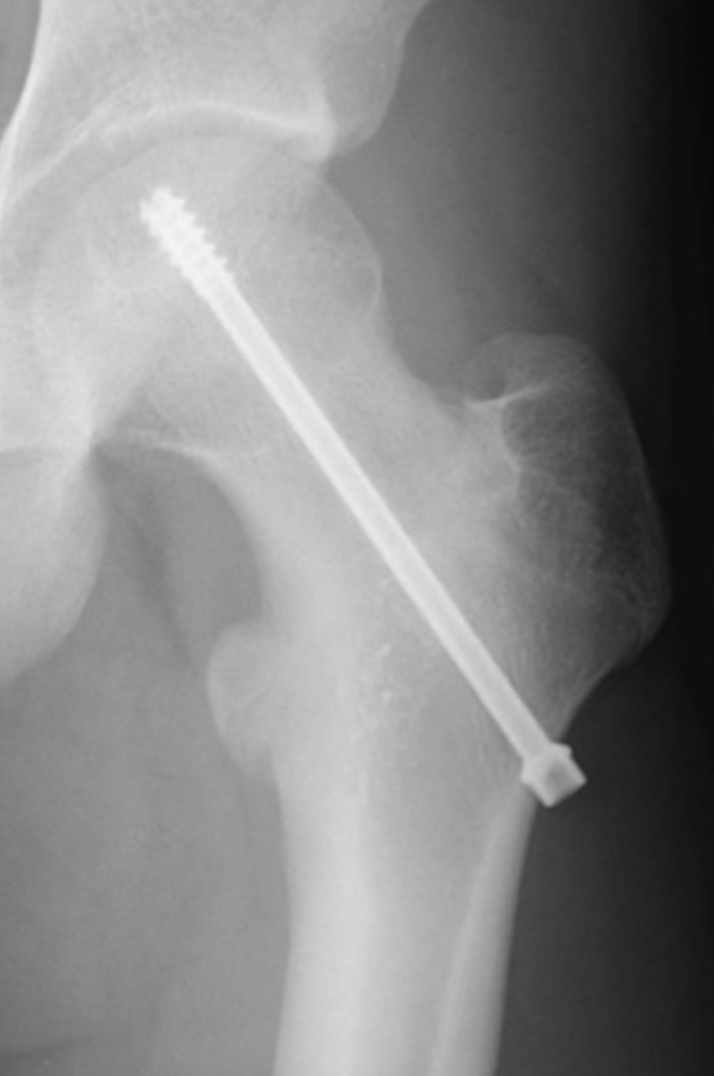

Als de verplaatsing van de kop beperkt is zal deze via een kleine incisie met een schroef gefixeerd worden.